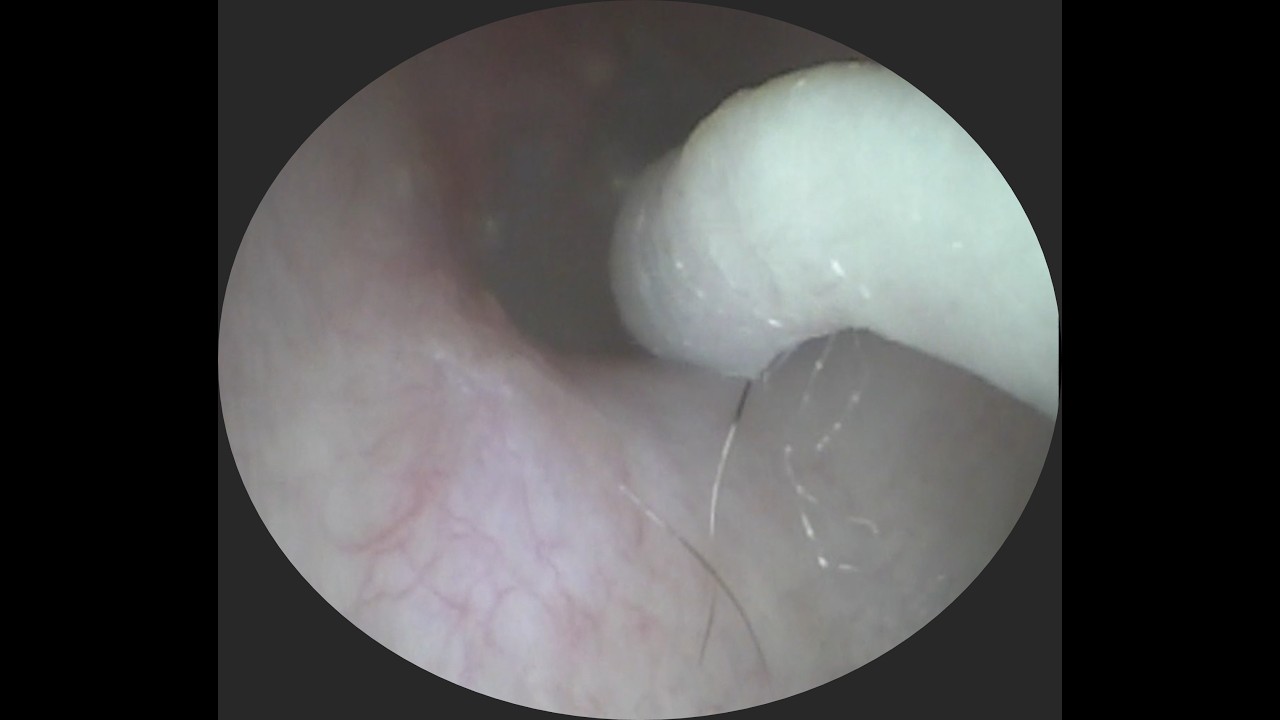

奥まで押し込まれた耳垢を救出! #イヤーエステ #耳掃除 #eariss #イヤーエステ #耳掃除 #耳かき動画 #耳美人クリエーター

公開日:2026/05/11